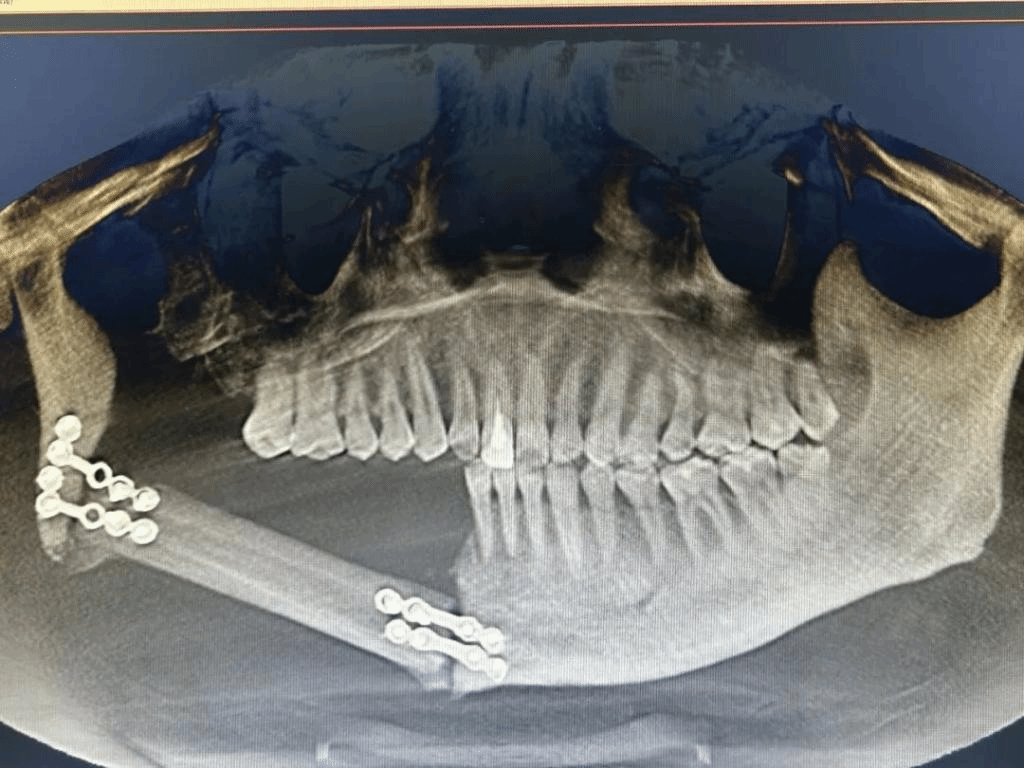

肿瘤诊断影像(左)肿瘤切除并移植后(右)

31岁的李先生于7个月前检查出右侧下颌骨巨大成釉细胞瘤,新疆医科大学口腔医(学)院口腔颌面肿瘤外科龚忠诚教授团队为他实施了右侧下颌骨扩大切除手术,利用数字化外科技术将患者小腿腓骨移植至右侧下颌骨,实现下颌骨的精确修复,成功恢复了下颌骨和面部外形。